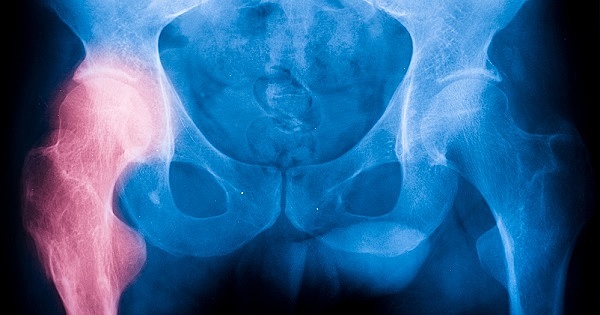

• Actualidad de la artroplastia

Actualidad de la artroplastia

Vástago ha pasado de acero a aleaciones de cromo – cobalto y titanio.

Cabeza femoral se ha pasado de acero a cromo – cobalto y cerámicos.

Se busca eliminar el uso del cemento para la fijación de los componentes protésicos introduciendo nuevas técnicas de fijación como son el bloqueo mecánico y el recubrimiento de los componentes con hidroxiapatita para intentar que el tejido óseo se una químicamente a la hidroxiapatita, y que sea dicha unión la que produzca la fijación del implante.